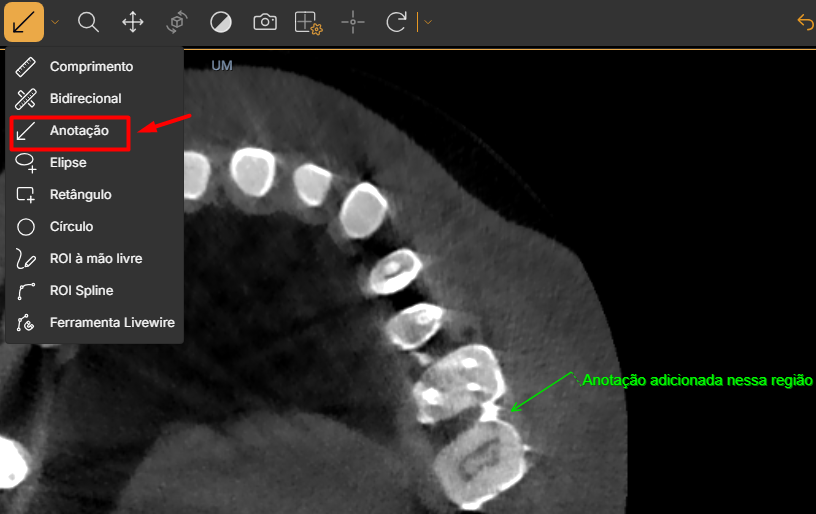

3. Anotação (Annotation)

Permite escrever observações diretamente na imagem. Basta clicar no ponto desejado e digitar o comentário. É útil para marcar áreas de interesse e registrar observações clínicas ou técnicas.

Uso prático: Clique no ponto onde deseja colocar a anotação e arraste o mouse para criar a seta. Depois, no menu de três pontinhos ao lado do ícone de olho, selecione “Renomear” e digite o texto da anotação.